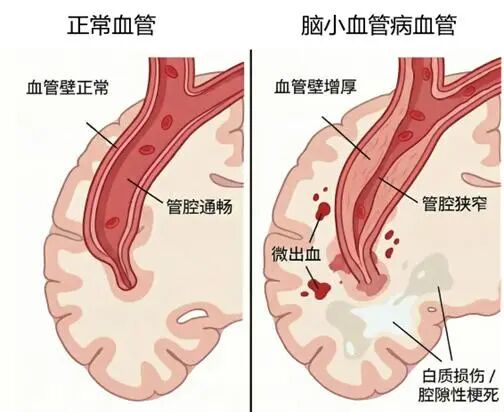

脑小血管病,指大脑内直径小于200微米的微小血管(包括小动脉、毛细血管、小静脉)发生退行性病变、堵塞或轻微渗漏,就像脑部深处的“微小水管”慢慢老化、不通畅,进而导致脑组织慢性缺血缺氧,神经功能出现渐进性损伤。

它和我们常说的急性大中风有明显区别:大中风发病急、肢体偏瘫等症状突出,容易被及时察觉;而脑小血管病起病极为隐匿,早期几乎没有特异性症状,进展缓慢,极易被当成正常衰老忽视。临床数据显示,60岁以上人群发病率超30%,90岁以上人群接近100%,也是诱发血管性痴呆、老年人反复跌倒的主要元凶。